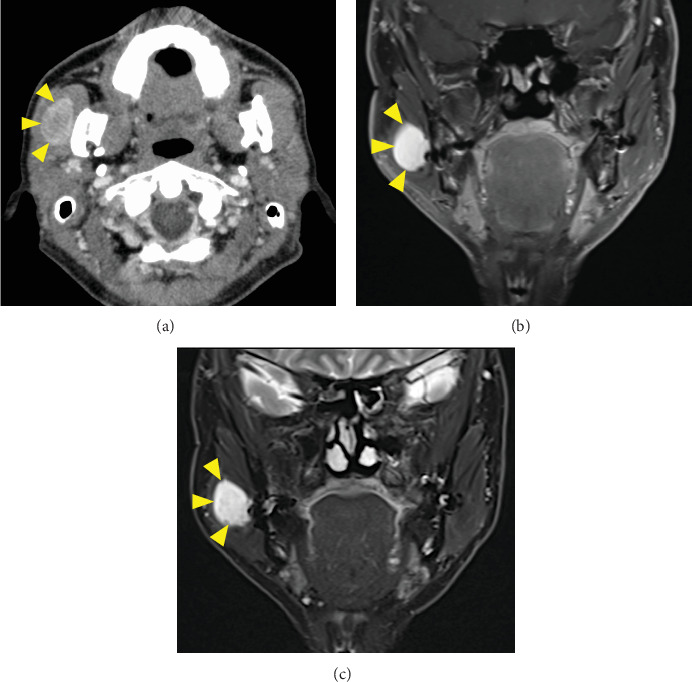

We present a case of solitary neurofibroma in the masseter muscle that was excised via the high perimandibular approach (HPMA). A 52-year-old Japanese man complained of an uncomfortable feeling in his right buccal region. On examination, the buccal mucosa appeared normal, and overall, there were no skin disorders on the patient's body. Computed tomography revealed a well-defined 33 × 22-mm mass in the right masseter muscle showing a low density in the center and a slightly higher density at the margin of the mass. Magnetic resonance imaging also showed a hyperintense area on T1-weighted and T2-weighted images in the masseter muscle. An excisional biopsy was scheduled for the diagnosis of the intramasseteric mass. It was performed via the HPMA with the patient under general anesthesia. The final diagnosis was a neurofibroma. The patient recovered after the surgery without postoperative complications, including facial nerve damage and trismus. He was satisfied with the esthetic outcome, and the tumor has not recurred over a 24-month follow-up period. Altogether, these outcomes indicate that the HPMA is an effective and useful option for excision of a tumor in the masseter muscle.